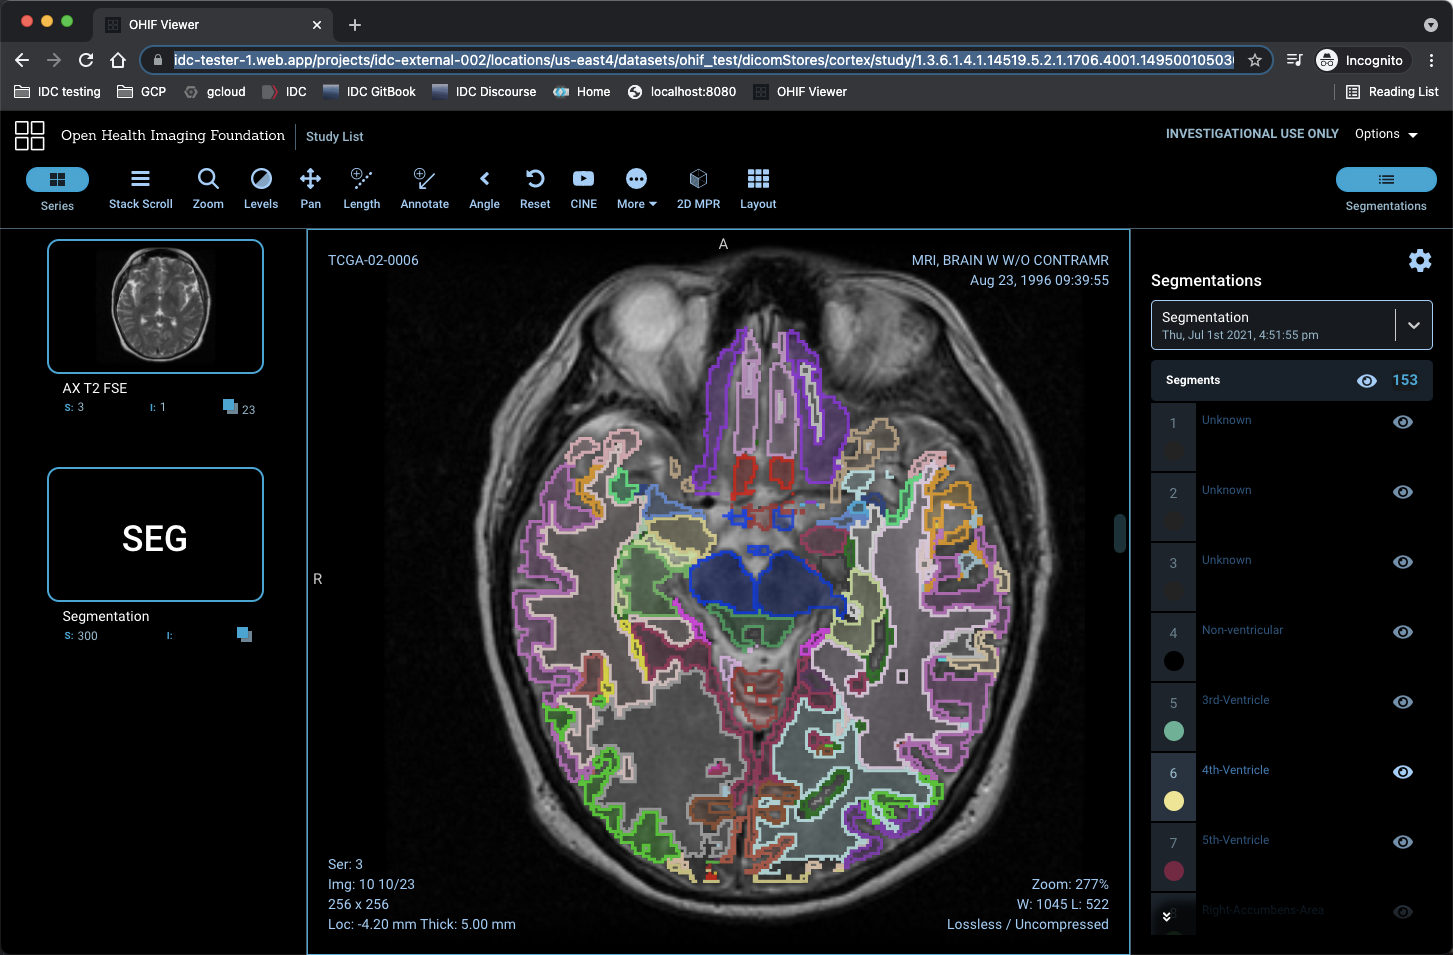

This is a parcellation run through the Imaging Data Commons framework, visualized online using OHIF: